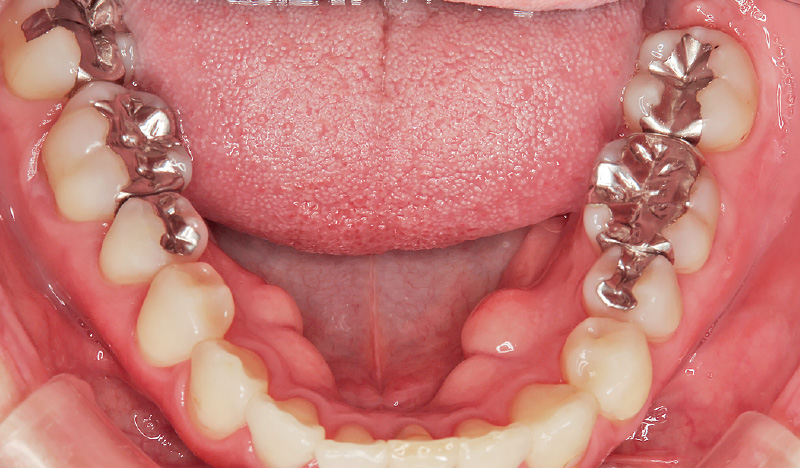

症例2-1 50代女性。金属アレルギーを発症し、メタルフリー治療を希望され来院。皮膚科でのアレルギー検査を経て、下顎右側から治療を開始。 -

症例2-2 メタルインレーを除去。補綴物のの下にう蝕の再発がないか慎重にチェックした。(「ルナビューショット」で撮影した動画より抽出) -